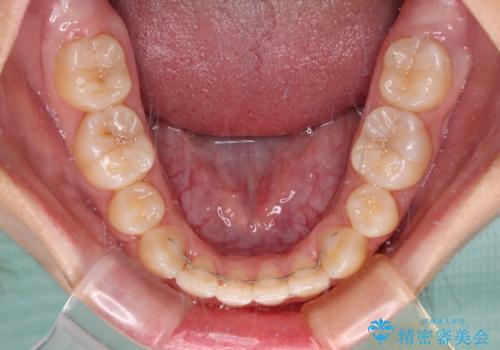

奥歯の咬み合わせが理想的であり、歯の移動に時間のかかる出っ歯でもなかったため、2年程度で治療を終えることを目標としましたが、無事に予定通りの2年間で終えることができました。